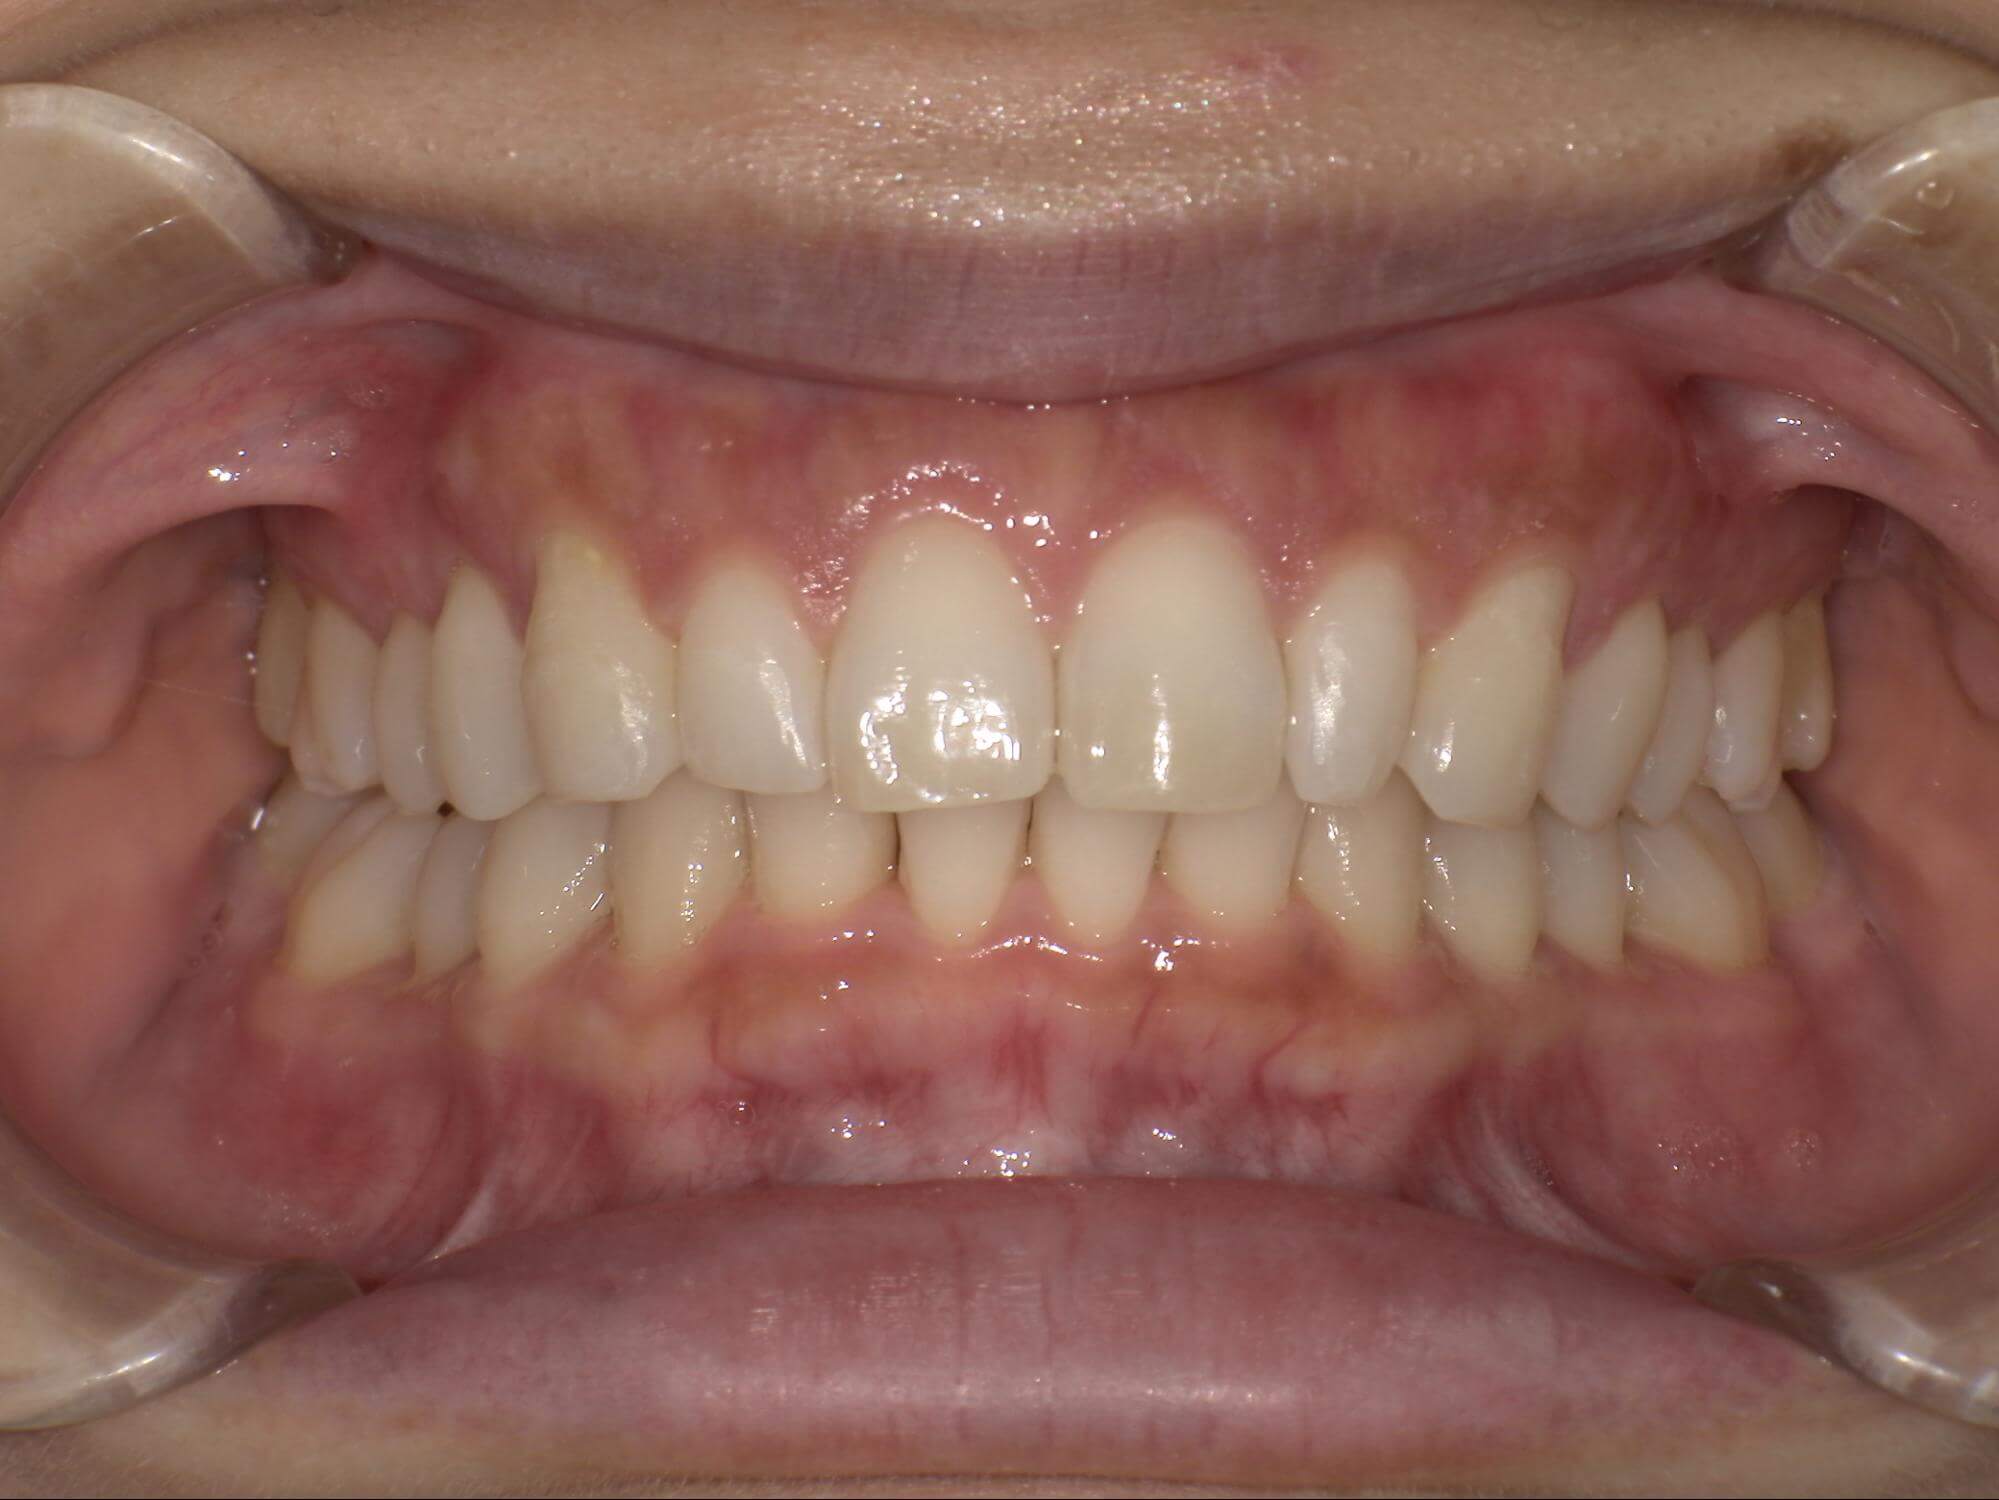

| 年齢・性別 | – |

|---|---|

| 主訴 | 叢生が気になる |

| 治療期間・回数 | 2年 |

| 費用 | 935,000円 |